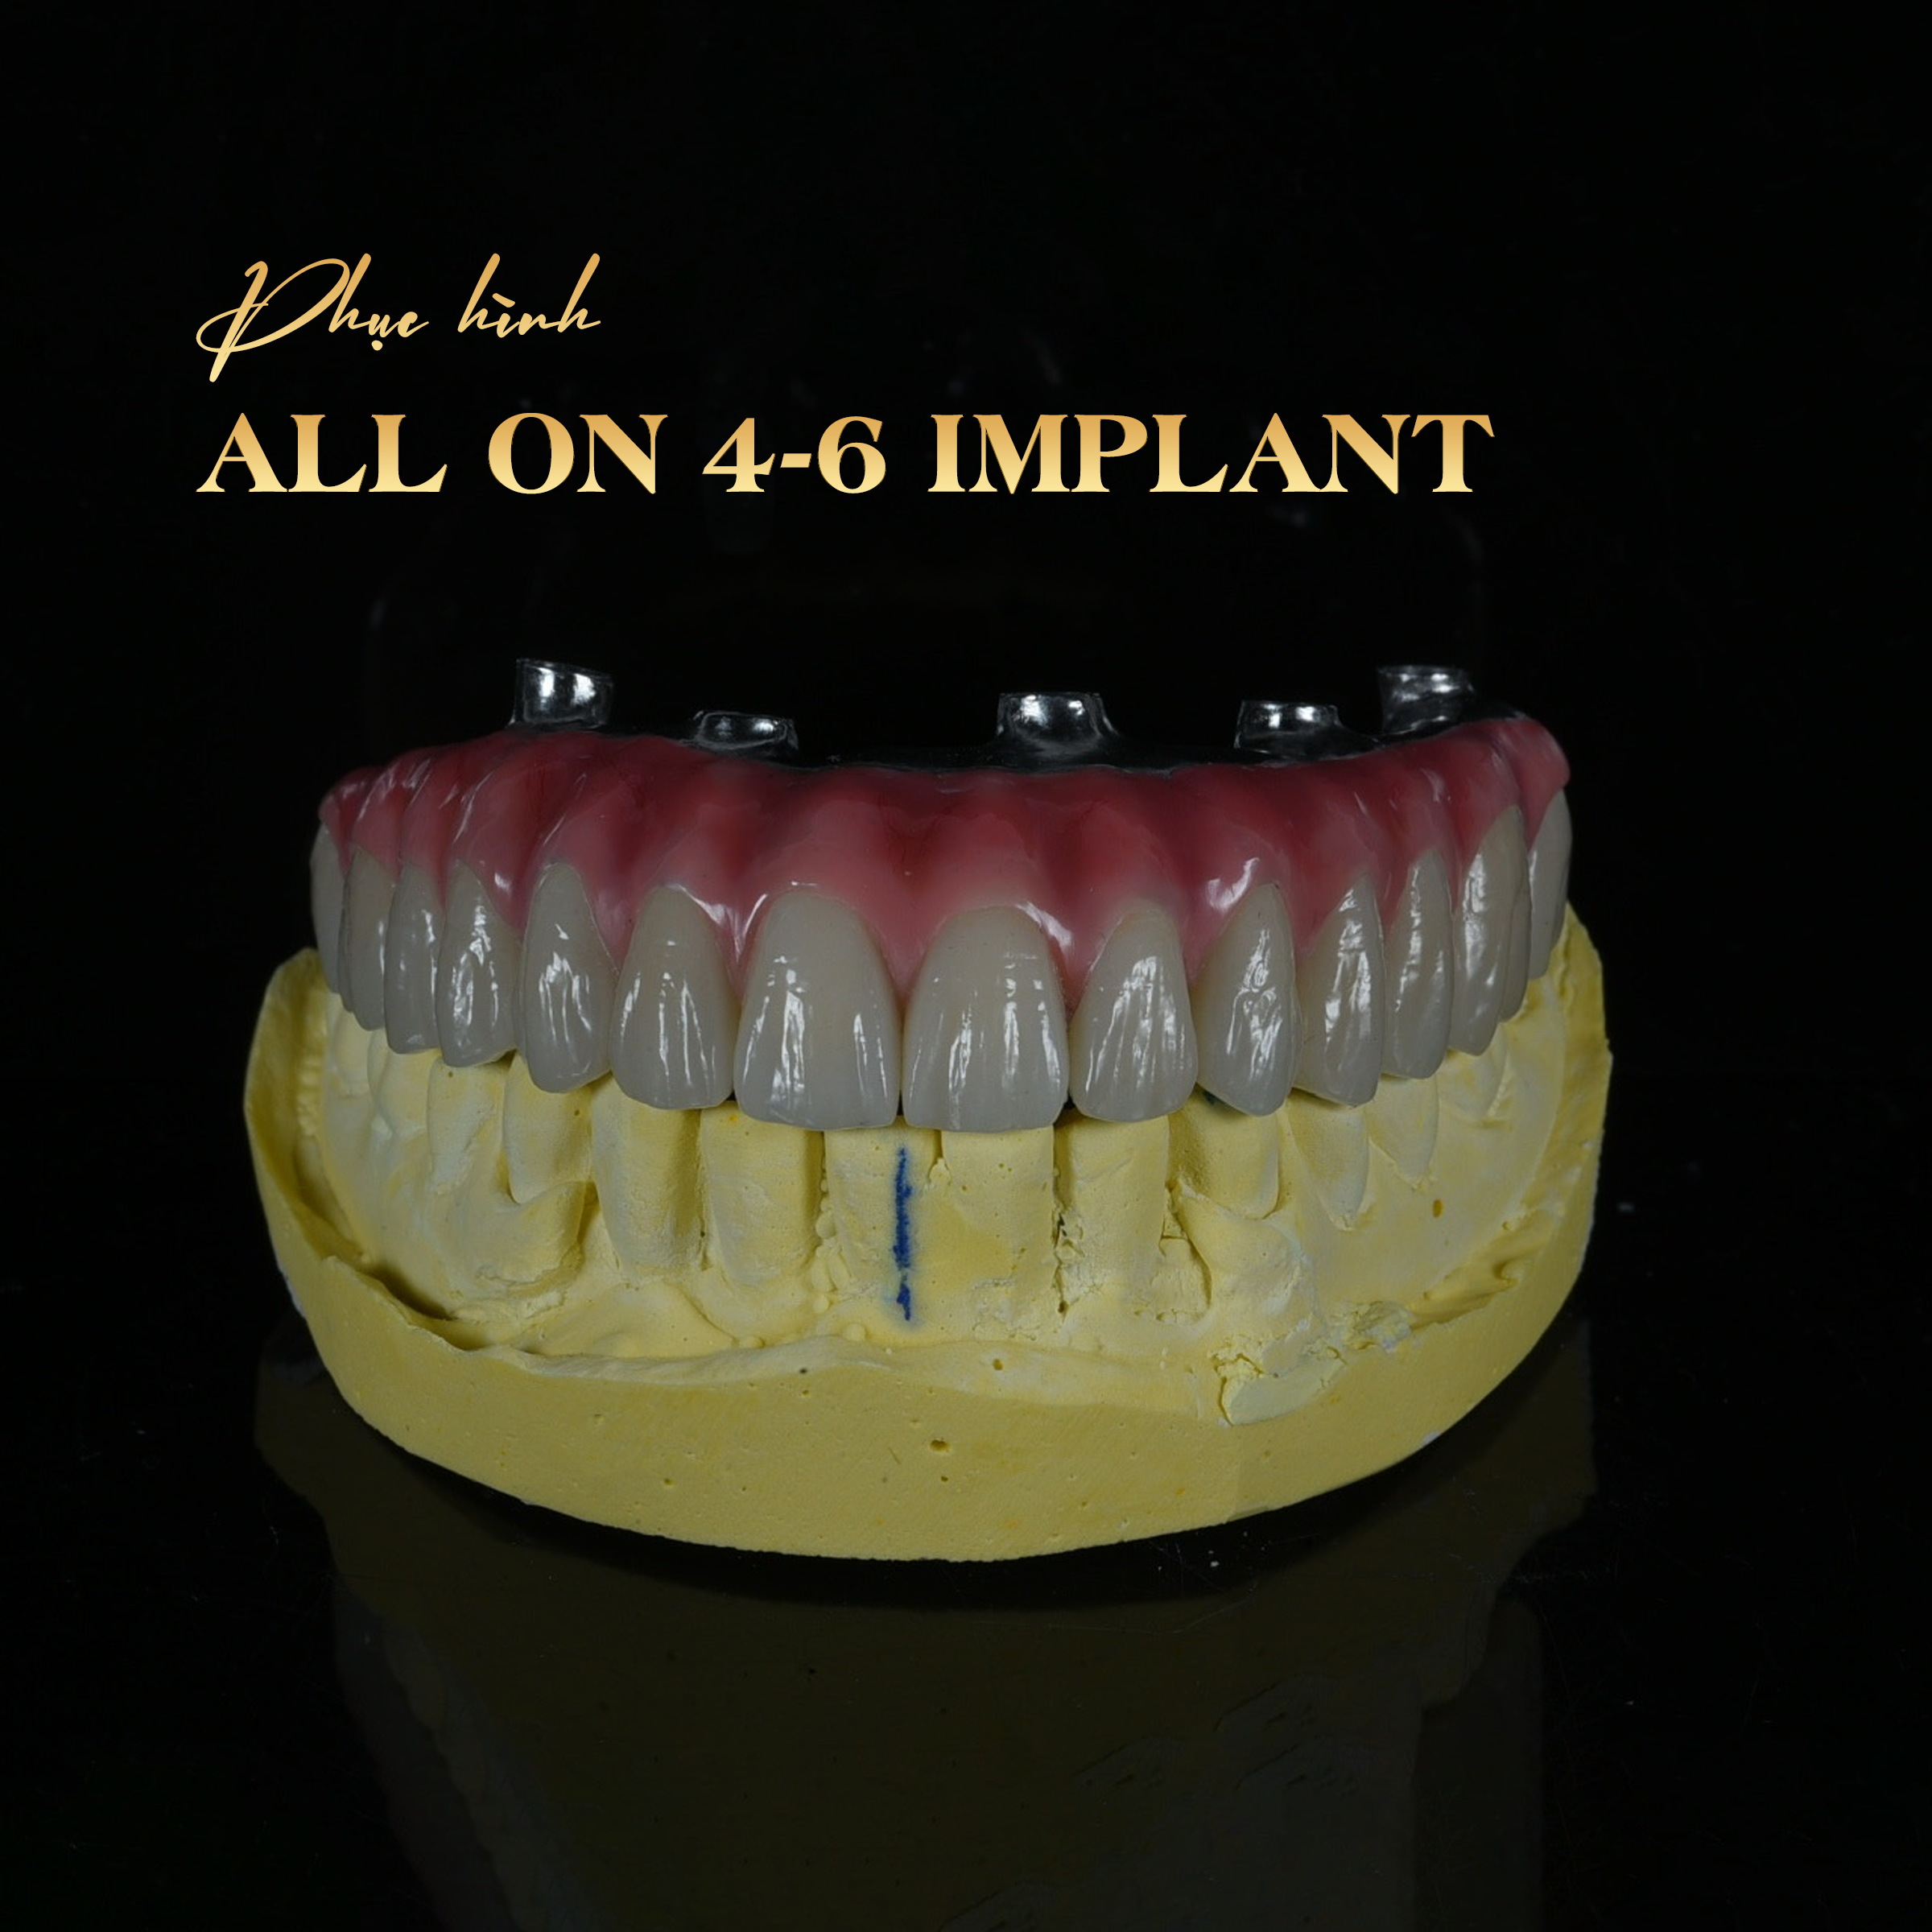

ALL ON 4 – 6 IMPLANT

All-on-4 và All-on-6 là kỹ thuật cấy ghép Implant toàn hàm tiên tiến, giúp phục hồi toàn bộ răng mất chỉ với 4 hoặc 6 trụ Implant. Phương pháp này mang lại hàm răng cố định, thẩm mỹ và ăn nhai vững chắc gần như răng thật.

– Trên các trụ này, gắn cầu răng cố định gồm 10–14 răng, phục hình toàn bộ hàm trên hoặc hàm dưới.

– Thẩm mỹ cao: Thiết kế ôm sát nướu, màu sắc tự nhiên, giúp gương mặt trẻ trung hơn.